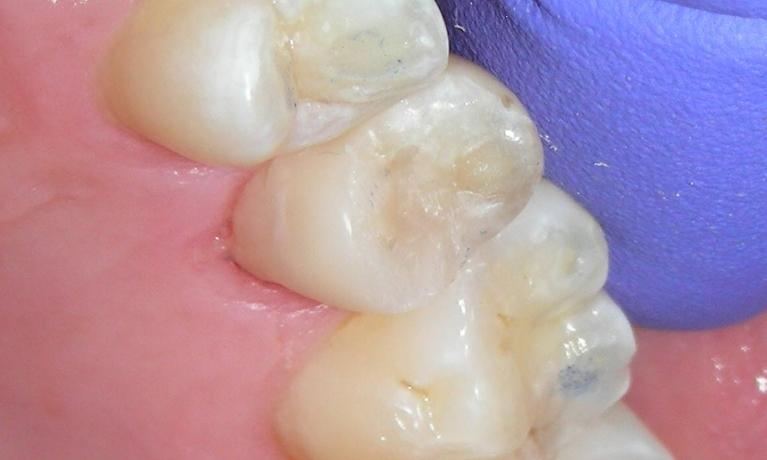

Diagnosis with theLED Transilluminator

The LED Transilluminator is an exciting new instrument that can let us “see into the inside of a tooth by lighting it up like a light bulb.

While in no way does it eliminate the need for dental X-rays, it provides another tool to diagnose decay, cracks and other conditions that might be missed by other methods.